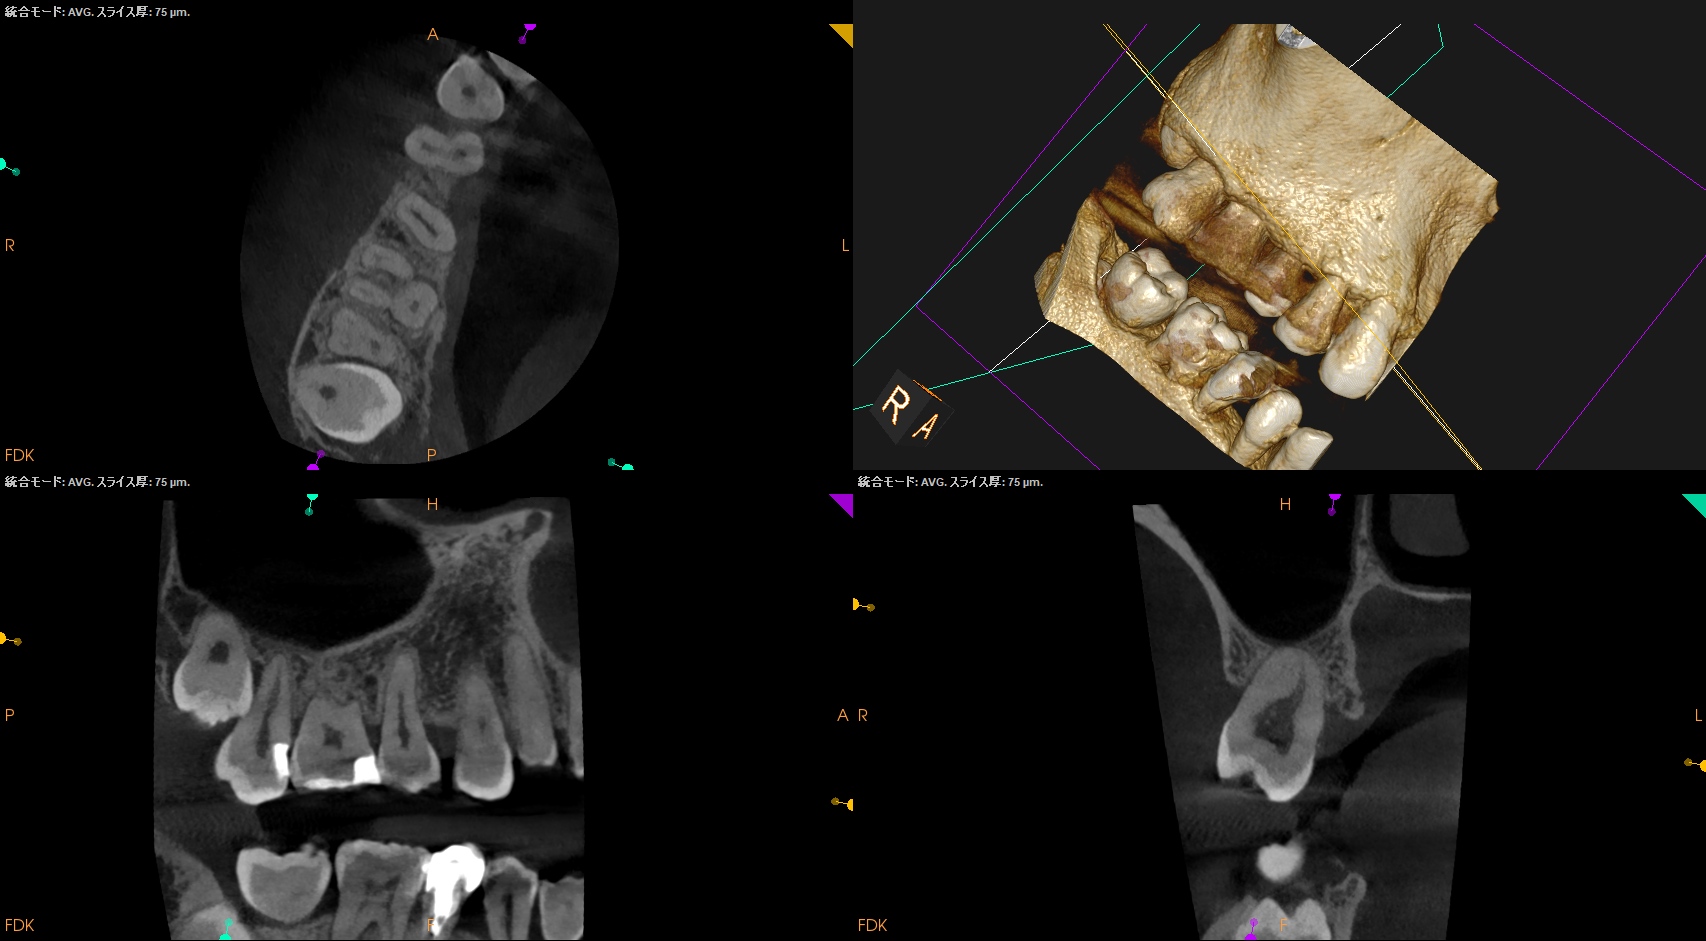

初診時と比較した。

問題が劇的に解決していることがわかる。

また、最終補綴も既に装着されていることからこの日で終診とさせていただいた。

Intentional Replantationを行なっても、それは, “長く持たない治療” ではなかったのだろうか?という話は横に置いておいて、

Intentional Replantationでなければこの歯の問題は解決できなかっただろう。

このように歯内療法外科(歯根端切除や意図的再植)ができなければ歯内療法のリングには立てないのである。

これが(Intentional Replantationが)歯の保存には必要な技術であるということがまたしてもこの記事でもわかるだろう。